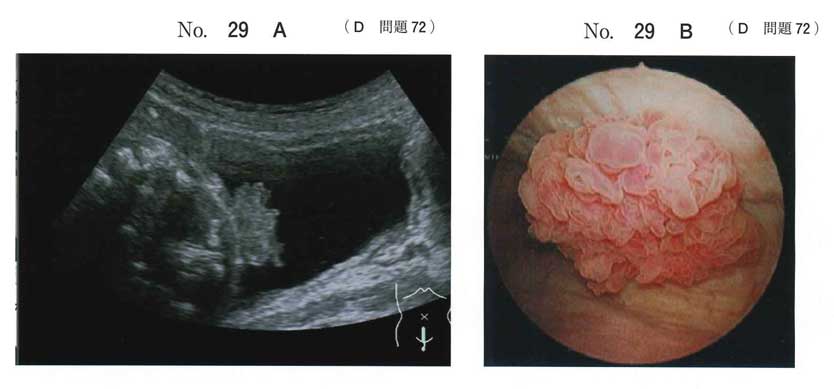

泌尿器科指導医です。頚部の腫瘍ならcも起こり得ますが膀胱鏡所見をを見る限り後壁〜頂部腫瘍と思われるのでcは否定的です。よってabeです。